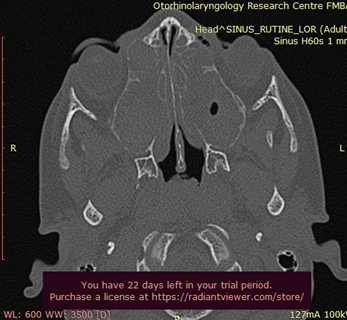

Обычно врач начинает со сбора подробного анамнеза и физического осмотра. Затем может предложить провести серию тестов, таких как анализ крови, анализы мокроты, рентген или компьютерную томографию грудной клетки и околоносовых пазух, дыхательные тесты (спирометрию), тесты на визуализацию реснитчатого эпителия, консультацию генетика.

Рисунок: КТ пазух носа при синусите